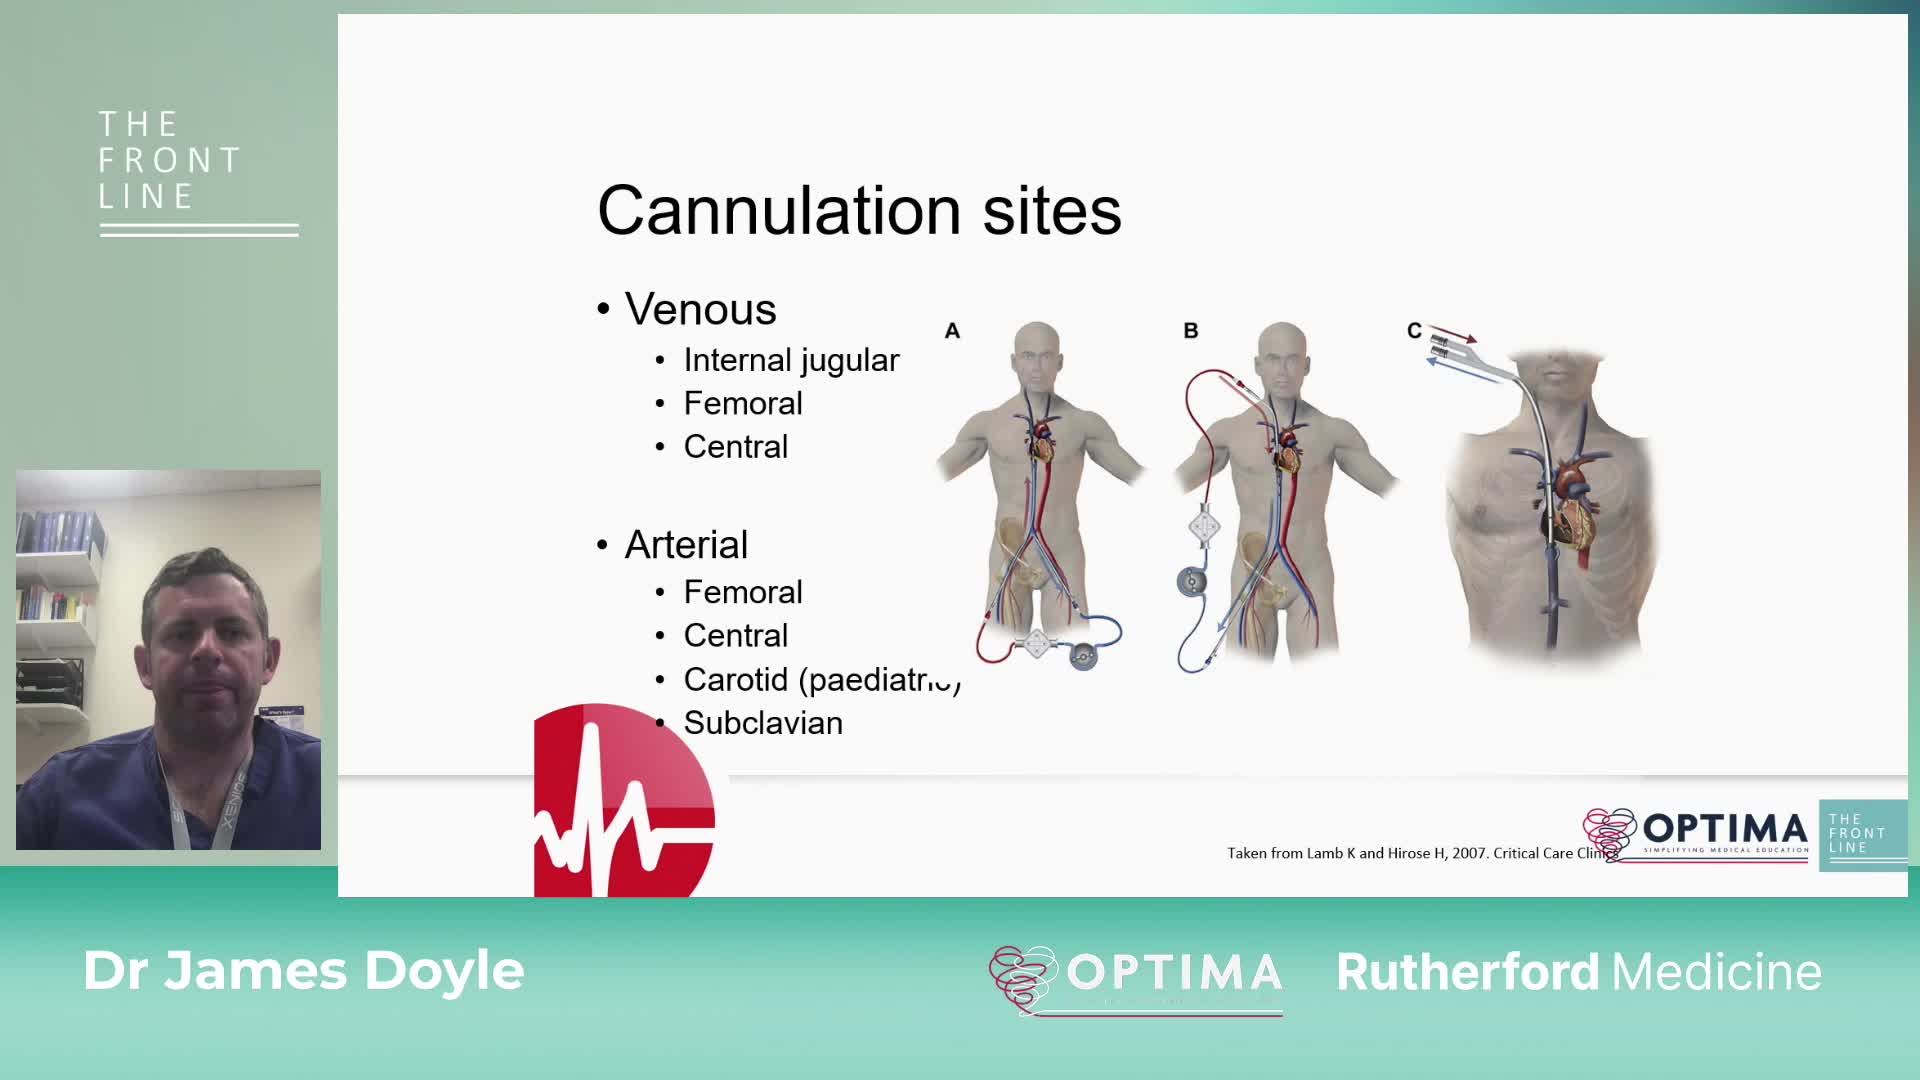

COVID-19: The Front Line. The Role of Extra Corporeal Membrane Oxygenation (ECMO) in the treatment of severe COVID-19